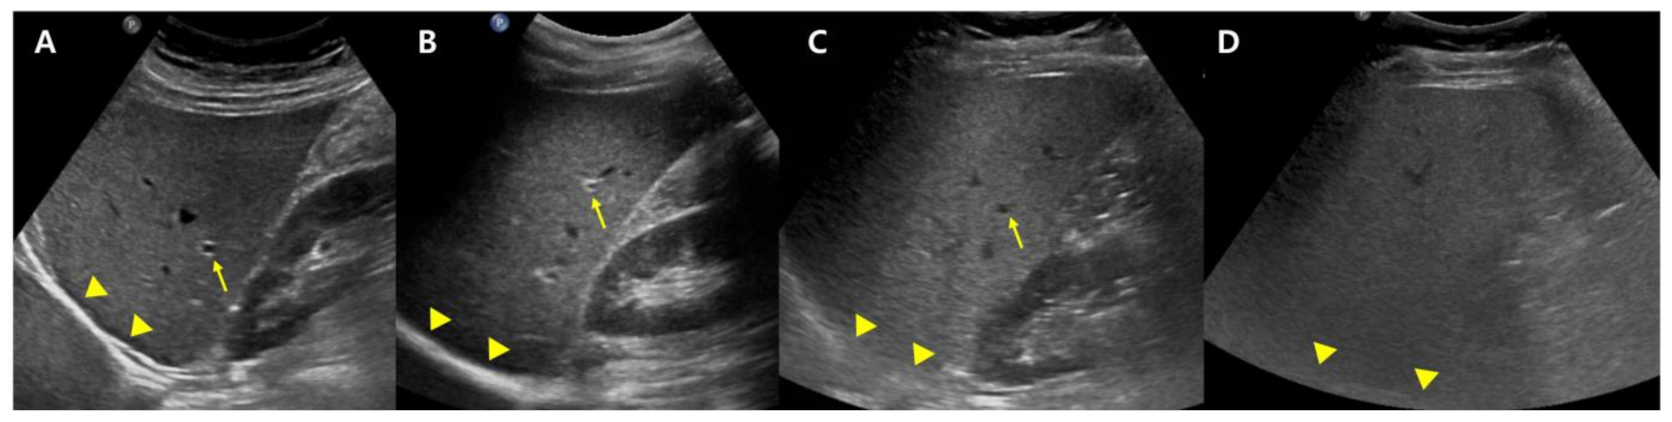

Conventional US carry disadvantages that are mostly due to inter-observer bias, though the technique can be made more objective in many ways, most straightforwardly, by normalizing the signal to the cortex of a healthy kidney. The liver-to-kidney ratio (hepatorenal index) (Figure 2) can be used to improve the technique and it has been useful in detecting liver steatosis [22,23]. However, the hepatorenal index has limitations in some patients as a result of the comorbid existence of kidney disease and anatomical variations, and it has been shown to struggle between differentiating absent and mild steatosis [24].

Figure 2. Conventional US of a healthy liver (A) and severe hepatic steatosis (C) with hepatorenal index (HRI) (B,D). Normal hepatic parenchyma echogenicity shows well-visible intrahepatic structures such as the portal vein, hepatic vein, and liver parenchyma (A). The HRI measures 1.22 (35.1/28.8, normal < 1.5) in a healthy liver (B). Severe hepatic steatosis shows poorly visible portal vein wall echo and hepatic vein (C), and the HRI measures 5.13 (66.8/13.0) (D).